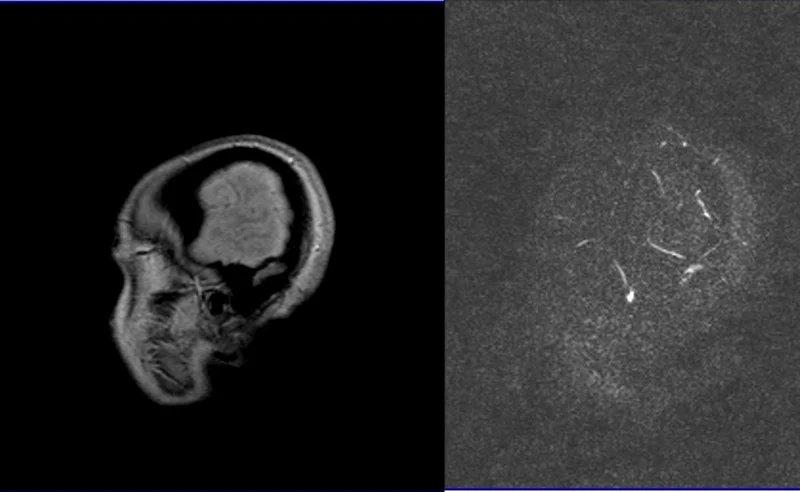

MRV brain phase contrast(PC) 3D images

Post processed MIP images from 3D rowdata